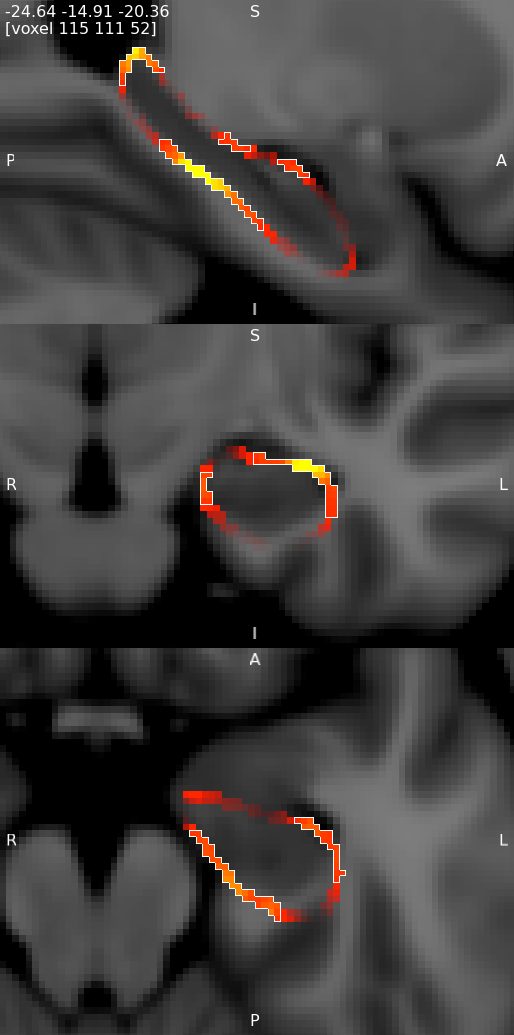

Results from randomise can be viewed in the standard orthographic or lightbox views in FSLeyes. To distinguish the direction of the changes see the description in the section on randomise above.

Viewing results in 2D

A useful option when displaying statistical results is to view the statistic image (e.g. the f-statistic, t-statistic image, etc), and to highlight significant regions with the corrected P-value image. This can be accomplished in FSLeyes like so:

- Start up FSLeyes, and add the following as overlays, ensuring that they are ordered in this way in the overlay list:

- the corrected P value image, e.g.

con1_dis2_L_Hipp_rand_clustere_corrp_fstat1.nii.gz - the statistic image that you want to visualise, e.g.

con1_dis2_L_Hipp_rand_fstat1.nii.gzto display the F-statistics from therandomisecall above. - The MNI152 1mm standard template

- Open the overlay display dialog (the gear button at top-left).

- Select the P-value image in the overlay list, and in the overlay display dialog change these settings:

- Overlay data type to 3D/4D mask image

- Show outline only selected

- Select the statistic image in the overlay list, and in the overlay display dialog adjust the display settings as desired - for example, you can set up a red/blue positive/negative colour display suitable for many statistic values with the following settings:

- -ve colour map selected

- First colour map set to Red-Yellow

- Second colour map set to Blue-Light blue

- Modulate alpha by intensity selected - this causes regions with a low value to be made transparent

- Display range and Modulate range adjusted as desired